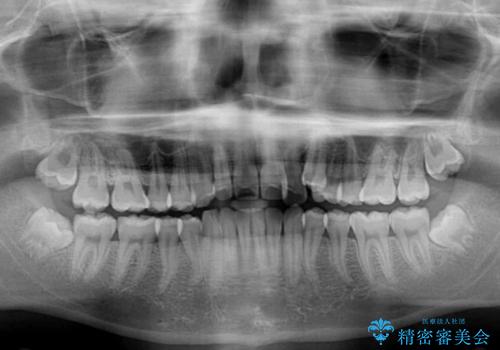

- 八重歯を気にして来院された患者様です。

八重歯が著しいため、抜歯矯正も視野に入れて検討しましたが、臼歯の咬合関係は正常に近かったので、非抜歯矯正で進める方針としました。

上顎骨の幅が狭く、奥歯がクロスバイトとなっていたため、急速拡大装置を用いて上顎骨を側方拡大し、八重歯を収めるスペースを獲得しつつクロスバイトを改善することとしました。